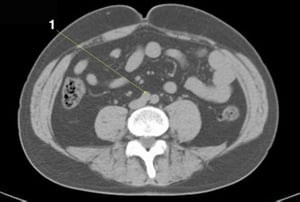

CT-Scan von Abdomen und Becken mit normaler Anatomie ohne Kontrastmittel (Folie 12)

1 = linke Nierenvene.

© Springer Science+Business Media